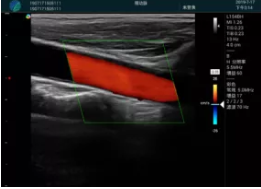

頸動(dòng)脈血流充盈飽滿,無外溢

2001年美國健康護(hù)理研究和質(zhì)量監(jiān)督局(AHRQ)批準(zhǔn)了一項(xiàng)關(guān)于提高患者安全性的報(bào)告,建議:在頸內(nèi)靜脈中心置管術(shù)時(shí)使用超聲引導(dǎo)。此后超聲引導(dǎo)穿刺被用于幾乎所有的急診穿刺操作,尤其是血管穿刺。

便攜超聲在急診穿刺中的應(yīng)用:

* 提高了穿刺成功率

* 減少了穿刺損傷及并發(fā)癥

* 縮短了操作時(shí)間

* 減輕了患者痛苦